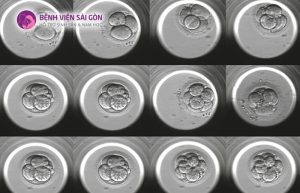

1. Sinh thiết phôi ngày 3

Ở giai đoạn phôi ngày 3, phôi thường chỉ có khoảng 6–8 tế bào. Việc lấy 1 tế bào lúc này đồng nghĩa với loại bỏ 12–15% tổng số tế bào của phôi, nên nguy cơ ảnh hưởng đến sự phát triển là tương đối cao.

2. Sinh thiết phôi ngày 5–6 (phôi nang)

1. Phôi có khả năng “tự sửa chữa”

Phôi nang có tính linh hoạt sinh học rất cao. Các tế bào lớp TE có khả năng:

- Tăng sinh bù trừ

- Tái cấu trúc nhanh sau khi sinh thiết

Nhiều nghiên cứu cho thấy, sau sinh thiết:

- Phôi vẫn tiếp tục nở

- Khả năng làm tổ không giảm đáng kể so với phôi không sinh thiết